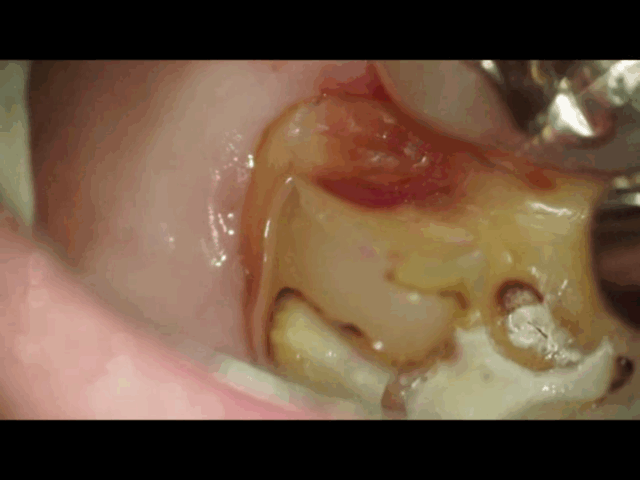

う蝕検知液(虫歯を赤く染める液)を使用して染まった虫歯を確認して削り取ります。

深くまで虫歯があるので慎重に少しずつ削り取ります。 -

虫歯を染め出すだけではなく、エキスカという先端が耳かきのようになっている器具を使って、手でガリガリと少し削ります。硬さや削りカスを見て虫歯か判断することもよくします。虫歯は軟かいのでボロボロと削れてしまうのは虫歯と判断できます。

神経の近くまで削っている時は、一気に削るのではなく、慎重に少しずつ削ります。 -

虫歯を削っていくと神経の穴が露出しました。

じんわりと赤くなっているので神経からの出血が確認出来ます。